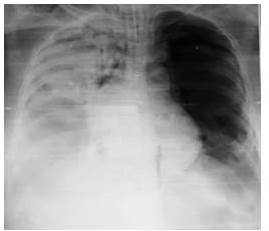

En vista de estos resultados y por el incremento de la sintomatología de disnea a pequeños esfuerzo, tos persistente, taquicardia, y la aparición de disfagia, se solicita control radiológico previo al ingreso en donde se evidencia en la radiografía tele de tórax posteroanterior atelectasia pulmonar total del pulmón derecho producto de la compresión por la gran lesión tumoral, así como del material mixoide (gelatinoso) que produce este tipo de pulmón el cual posiblemente este inundando al trato bronquial principal derecho (Figura 3).